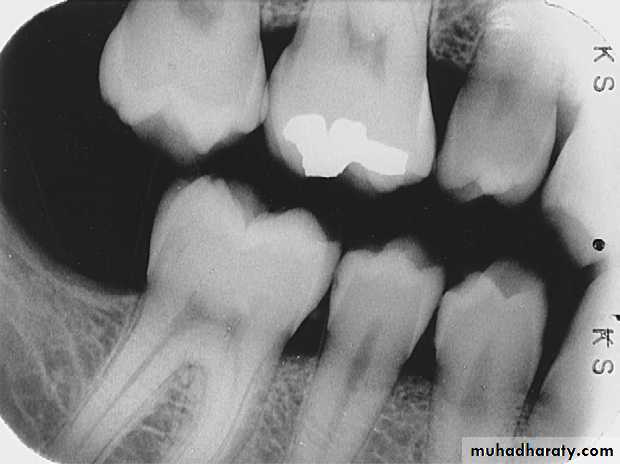

Rampant CariesRampant caries is advanced and severe caries that affects numerous teeth

Rampant caries is typically seen in children with poor dietary habits or in adults with decreased salivary flow.